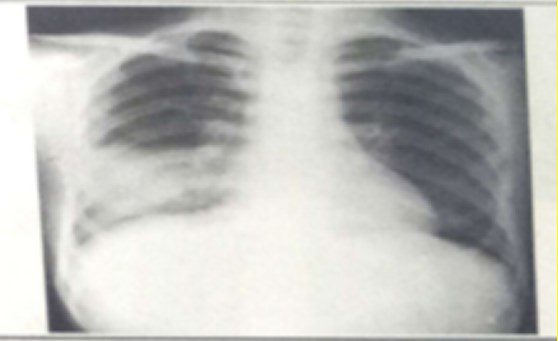

试题:男性,26岁,受凉后寒颤高热,咳嗽,咳铁锈色痰5天(2分)

A.肺癌

B.气胸

C.正常胸片

D.肺炎

答案:D